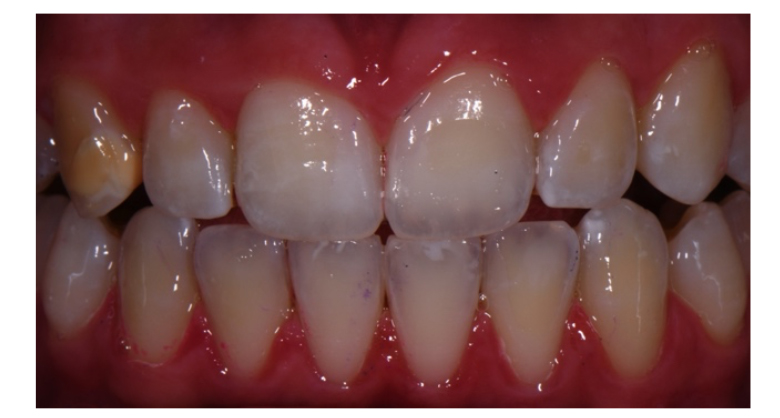

Al follow up dopo un mese (T1) osserviamo un miglioramento della WSL dell’incisivo 2.1. Infatti mentre alla prima visita (T0) la WSL dell’incisivo 2.1 si presentava come due lesioni sovrapposte, una profonda e una superficiale, al controllo dopo un mese si nota una riduzione della lesione più esterna. In accordo con la paziente decidiamo di proseguire con questa terapia. Al secondo follow up, a distanza di un ulteriore mese (T2), osserviamo che la WSL dell’incisivo 2.1 si è ridotta ulteriormente e la sensibilità risulta essere sparita. Essa infatti presenta solo una lesione profonda (MIH) mentre quella più esterna da trattamento ortodontico è mimetizzata. La WSL del dente 3.2 e la BSL del dente 1.3 invece non mostrano nessun cambiamento. Decidiamo comunque di procedere con il medesimo protocollo per un ulteriore mese. Al terzo follow up sempre a distanza di un mese (T3), osserviamo che non c’è nessun cambiamento nelle WSL e scegliamo con la paziente e la madre di proseguire con un nuovo approccio terapeutico combinato. In questo caso la terapia prevede il supplemento di tre tecnologie: sbiancamento, microabrasione e infiltrazione.

È infatti grazie alla sinergia di queste quattro tecnologie che riusciamo a trattare con successo le WSL più profonde ed estese (fig. 2).